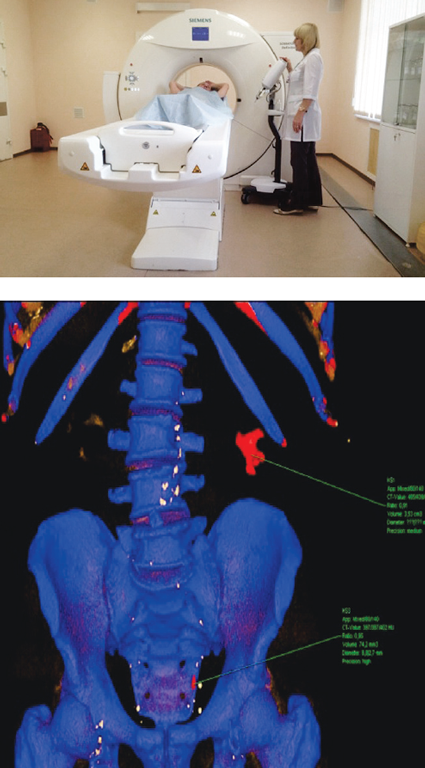

Синдром подвздошной венозной компрессии верифицируют по данным МРТ нижней полой вены или сосудов малого таза и КТ органов брюшной полости с контрастным усилением, флебографии, флеботонометрии, внутрисосудистого УЗИ. При обработке данных МРТ нижней полой вены и сосудов малого таза и КТ органов брюшной полости с контрастным усилением определяют критерии подвздошной венозной (вертеброартериальной) компрессии, которые включают в себя определение величины нижнего люмбарного лордозного угла (Lower lumbar lordosis angle, LLLA) (норма — 134,33–136,76°) и диаметра подвздошного венозного туннеля (Diameter of the iliac vein tunnel, IVTD) (норма — 4,18–4,50 мм) [23].